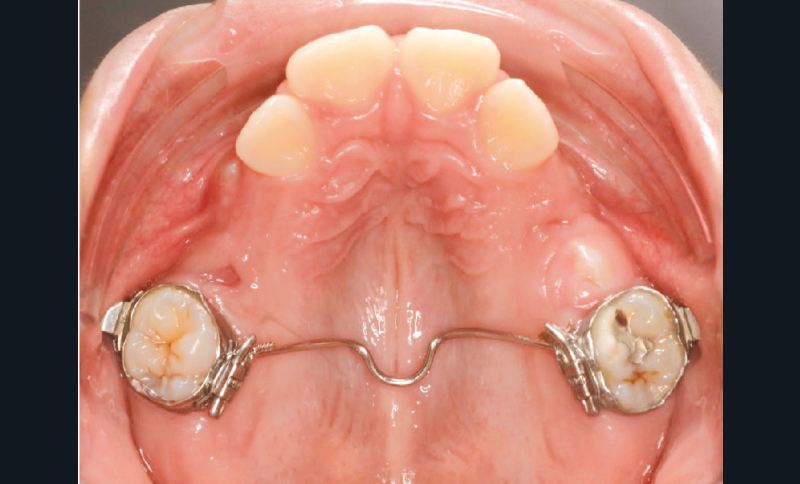

Lina, 8 ans et 5 mois, nous est adressée en consultation d’orthodontie dans le service de médecine bucco-dentaire de l’Hôpital Bretonneau en transfert avec absence des 2 prémolaires du secteur 1, alors que 44 et 45 sont présentes et que cette dernière manque de place pour faire son évolution sur l’arcade (fig. 1 et 2).

Un bilan radiologique 3D (Cone Beam CT) est prescrit dans le but d’évaluer, avec l’équipe de chirurgie du Dr Jean-Luc Charrier (Hôpital Bretonneau), la possibilité de transplantation d’une prémolaire du secteur 4 vers le secteur 1 et de définir le meilleur transplant possible entre 44 et 45. Sont analysées les dimensions du site receveur ainsi que l’anatomie, la position et l’état de maturation radiculaire des prémolaires candidates à la transplantation (fig. 3).